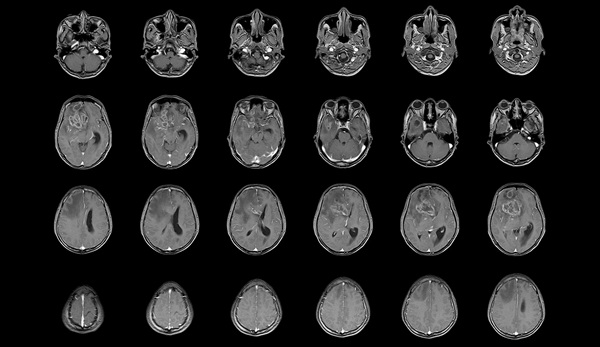

The MRI scans showed a statistically significant decrease in grey matter volume in the anterior cingulate cortex bilaterally of the brain, and in the right insula, in those participants with a history of heavy alcohol consumption during adolescence.